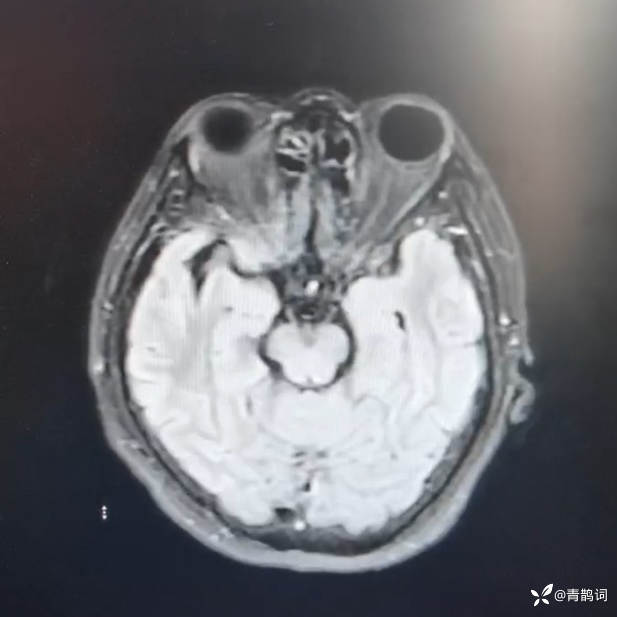

头部磁共振DWI及FLAIR: